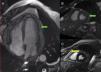

A)Ecocardiografía transtorácica (ETT) en plano de 4 cámaras que muestra la imagen de derrame (flecha azul) y engrosamiento pericárdico. B)Detalle del engrosamiento pericárdico (flecha verde) y del derrame (flecha azul), de características fibrinosas. C)Doppler pulsado del llenado a través de la válvula tricúspide que muestra variaciones respiratorias (flechas verdes) del 58%. D)ETT en plano 4 cámaras tras el tratamiento optimizado que muestra disminución del derrame y del engrosamiento pericárdico. E)Doppler pulsado del llenado a través de la válvula mitral con patrón normal.

Esta figura se muestra a todo color solo en la versión electrónica del artículo.